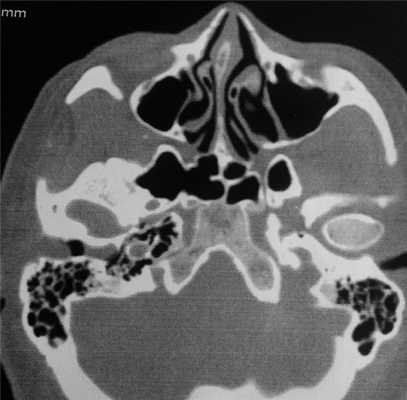

При компьютерной томографии (КТ) височных костей (рис. 1): в правом наружном слуховом проходе, субтотально его выполняя, тесно прилегая к сосцевидному отростку, определяется объемное образование размерами 27×15×18 мм, плотностью 37 ед. Х.

Рис. 1. Компьютерная томография пациента А., 45 лет: аксиальная проекция. Стрелкой указано образование наружного слухового прохода справа.